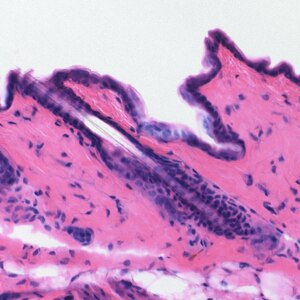

Alizarin (C.I. 75330) je bilo vrlo važno bojilo, pa se broć (bojadisarski broć, lat Rubia tinctorum) uzgajao na velikim površinama u Europi od 9. do potkraj šezdesetih godina 20. stoljeća kad su G. Graebe i K. Liebermann utvrdili kemijsku strukturu alizarina i tako omogućili njegovu sintezu i industrijsku proizvodnju, kojoj nije mogla konkurirati proizvodnja alizarina iz broća. Alizarin se upotrebljava za bojenje pamuka, vune i svile (uz močenje u aluminijskim solima u crveno, u kromnim solima u crvenosmeđe, a u željeznim solima u ljubičasto). Pamuk močen sulfatiranim uljem ricinusa upotrebom alizarina oboji se jarkocrveno. Složene soli alizarina s metalima služe kao pigmenti za izradu slikarskih boja i tinte, a ekstrakti kao bojila za histološke preparate.